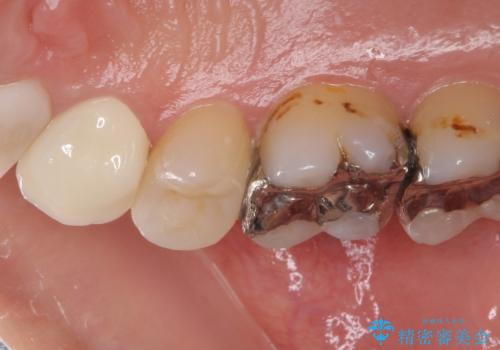

- 奥歯に痛みを感じるようになり、更にはその前の歯のセラミックが欠けてしまったとのことで来院された患者様です。

痛みがしばらく続いていたため、抜髄となる可能性を考慮しながら処置を行うこととしました。

処置後に痛みの状態を確認し、前歯のクラウンの再製作を同時に進めることとしました。

銀歯の下の虫歯はそれほど大きくなく、初回の処置以降、痛みを感じることはなくなりました。

セラミックインレー装着後も痛みが生じることはなく、神経の状態も正常な反応が認められました。